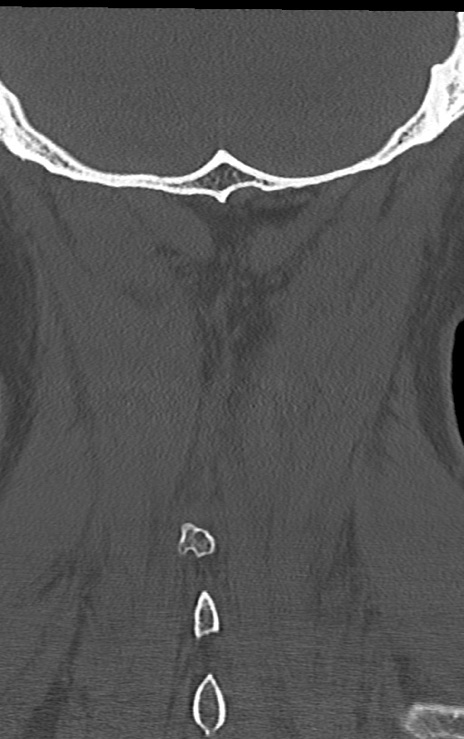

頚椎CT

矢状断像